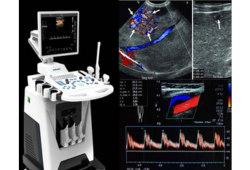

Radiology & Imaging

Accurate and timely imaging for diagnosis, monitoring and treatment planning.

We provide high-quality ultrasound, Doppler, digital X-ray and fetal scans with prompt reports and expert interpretation.

Ultrasound / Sonography

Abdominal, pelvic, thyroid and soft-tissue imaging.

Colour Doppler

Arterial and venous flow assessment; vascular mapping.